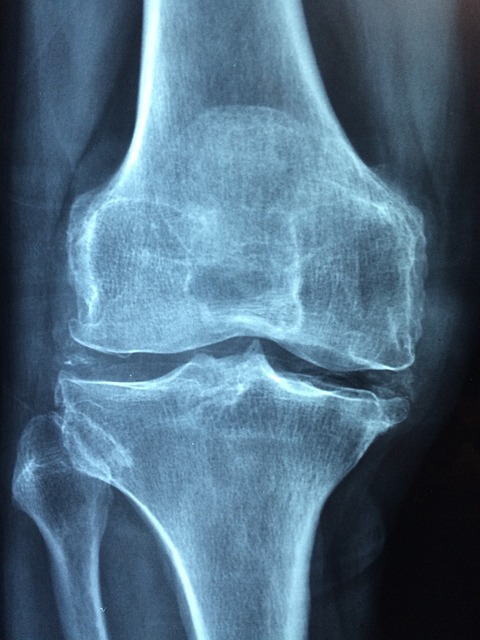

1. 궤양성 대장염과 류마티스 관절염

궤양성 대장염과 류마티스 관절염은 모두 자가면역 질환으로 분류되지만, 직접적인 연관성은 명확하지 않습니다. 그러나 일부 연구에서는 이 두 질환 사이에 일부 연결고리가 있을 수 있다는 증거가 제시되었습니다.

공통된 면역 메커니즘: 궤양성 대장염과 류마티스 관절염은 면역 시스템의 이상한 반응에 기인한 질환이며, 자가면역 반응이 발생합니다. 이들 질환에서 면역 시스템은 실제로는 정상적인 조직과 세포를 외부 공격으로 인식하고 공격합니다. 이러한 공통된 면역 메커니즘은 이들 질환 간의 연관성을 제안할 수 있습니다.

유전적 요인: 유전적인 요소도 궤양성 대장염과 류마티스 관절염의 발생에 영향을 미칠 수 있습니다. 가족력이 있는 경우, 두 질환의 발생 위험이 증가할 수 있습니다. 이는 유전적 요인이 이들 질환의 공통적인 기저에 영향을 줄 수 있음을 시사합니다.

관찰된 연관성: 일부 연구에서는 궤양성 대장염과 류마티스 관절염 사이에 통계적으로 유의한 연관성을 보고하고 있습니다. 예를 들어, 궤양성 대장염을 가진 환자에서 관절염 증상이 발생하는 경우가 더 빈번하게 보고되고 있습니다. 그러나 연구 결과는 일관성이 없으며, 직접적인 원인-결과 관계를 입증하기에는 충분하지 않습니다.

이러한 이유로 현재까지 궤양성 대장염과 류마티스 관절염의 직접적인 연관성은 명확하지 않습니다. 더 많은 연구가 필요하며, 질병 발생에 영향을 미치는 유전적 요소와 면역 메커니즘에 대한 더 깊은 이해가 필요합니다.